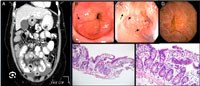

Hình 1

Viêm nang lông dạng vẩy phấn được mô tả đầu tiên bởi Aries năm 1930 xảy ra chủ yếu ở phụ nữ trung niên hoặc già hơn, những người này ít rửa mặt, nhưng sử dụng nhiều kem trang điểm và kem tẩy.Biểu hiện bởi đỏ mặt lan toả và có vẩy ở nang lông hoặc da bị xậm màu, nút sừng nhỏ ở nang lông làm cho da mặt lấm tấm như giấy ráp. Cảm giác chủ quan ngứa và cảm giác nóng bỏng, có cảm giác như kiến bò. Cạo da chứa lượng lớn Demodex spp.Mô bệnh học cho thấy chúng xâm nhập viêm nhiều tế bào Lympho xung quanh các mạch máu ở trung bì, không hình thành u hạt.

Hình 2

2. Viêm da Demodex giống dạng trứng cá đỏ:

Bệnh nhân có biểu hiện lâm sàng như sẩn và sẩn mụn mủ, đỏ da, có vẩy giống như trứng cá nhưng có những đặc điểm riêng.Bắt đầu đột ngột, tiến triển nhanh với các triệu chứng ngứa, rát, cảm giác như kiến bò trong bóng tối, đỏ da dai dẳng, nhạy cảm với ánh nắng và có vẩy da ở nang lông.

Hình 3

Tổn thương là những sẩn mụn nước, mụn nước mụn mủ, đặc biệt không có cồi hay nhân. Tổn thương không đối xứng, không có biểu hiện giãn mạch, thường có phối hợp viêm bờ mi. Tiền sử thường dùng thuốc bôi chứa corticosteroid, thường gặp trên bệnh nhân suy giảm miễn dịch và về mặt mô bệnh học thấy bạch cầu đơn nhân thâm nhập viêm xung quanh nang lông, đôi khi hình thành u hạt.

Hình 4

3. Viêm da do Demodex dạng trứng cá đỏ thể u hạt:

Bệnh biểu hiện sẩn đỏ, mụn mủ, abces ăn sâu và ở một bên mặt, tồn tại dai dẳng, không đáp ứng với điều trị thông thường. Thể này thường phối với hội chứng suy giảm miễn dịch mắc phải (có hay không có HIV). Mô bệnh học thấy tổ chức u hạt bao gồm tế bào khổng lồ chứa dấu vết của hiện tượng thực bào Demodex spp, có hoại tử ở trung tâm. Ngoài ra viêm da có thể kèm theo rụng tóc và viêm bờ mi, viêm bờ mi.